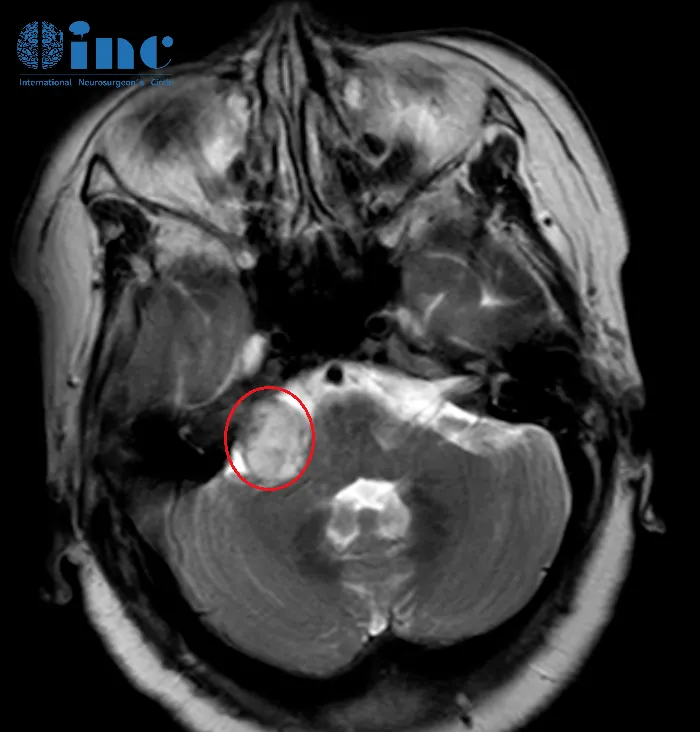

罹患囊性听神经瘤需要手术,但全切容易损伤面神经,无法控制面部表情,无法微笑,甚至无法闭眼...保神经又可能切不干净,可能又会复发。因此医生和患者常常陷入决策两难。 为什么囊性...

听神经瘤作为桥小脑角区最为常见的肿瘤,临床表现多样,比如听力下降、耳鸣、头痛、平衡失调,面部疼痛和麻木,这类肿瘤多见于30岁至60岁人群,很少见于年轻患者。 本期要分享的病例是...